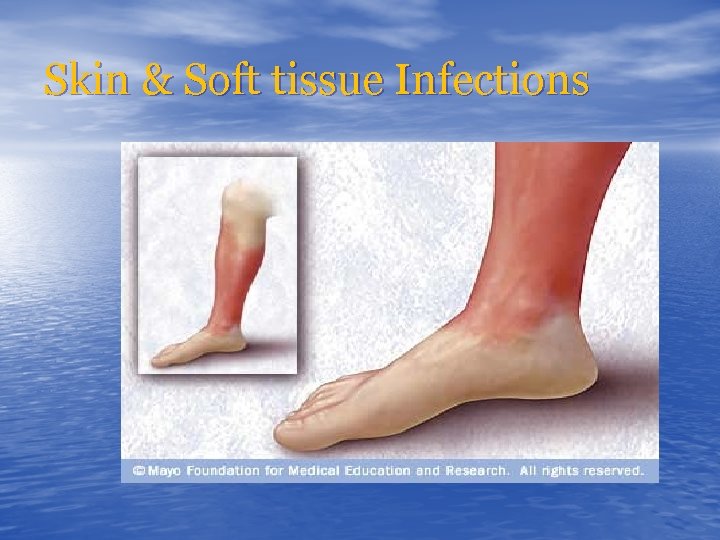

Skin & Soft tissue Infections

Skin & Soft tissue Infections

CELLULITIS

CELLULITIS

CELLULITIS

CELLULITIS

CELLULITIS

CELLULITIS